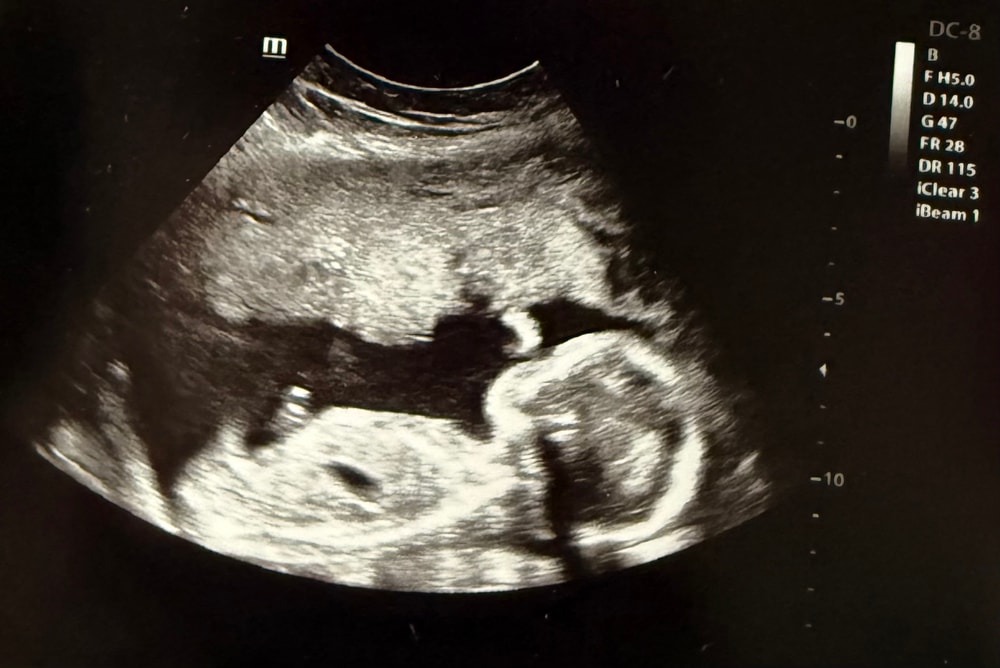

19 недель и 2 дня. Второй скрининг позади

Анализы, скринингиВот и мы добрались до второго скрининга. Время летит незаметно, уже 19 недель и 2 дня. По результатам все хорошо, все размеры соответствуют сроку, все органы и части тела на месте. Человек крутился, как юла, не давал себя измерить нормально.

Наконец, увидели, кто там прячется. Мальчик. Я, конечно, догадывалась, но все равно немного расстроилась. Хотела я девочку больше. Но уже не поменяешь 😅 придется привыкать к этой мысли. Врач мне говорит: «Значит придете еще». Ну уж нет, думаю. Уже и так почти 39. Это увлекательный аттракцион, но, пожалуй, я пас. С производством детей я на этом завязываю. Буду внуков ждать.

Срок совпадает с первым скринингом, и на неделю опережает срок по месячным. Так что пдр у меня на 6 января. Но думаю, что рожу в конце декабря, как бы вообще не на свой день рождения 😅

Шейка длинная, больше 40 мм, по всем остальным показателям тоже все хорошо, так что летим спокойно в отпуск. Настроение пока не чемоданное, хотя поезд уже ночью сегодня.